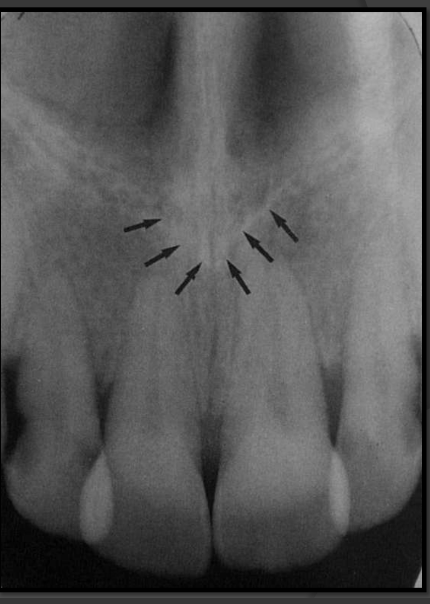

How does the incisive foramen present in a radiograph?

It is a radiolucency that presents between the roots of the maxillary centrals. It is variable in shape, size, and border.

How does the median palatine suture present in a radiograph?

A thin radiolucent line that runs directly between the maxillary incisors.